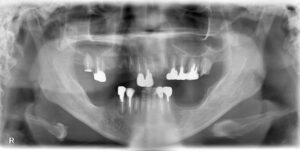

9/3に、全体的に歯を治して欲しいとの事で56歳女性が来院されました。

パントモ、アルバム、CTを撮り、

下顎の前歯部はジルコニアのブリッジ

上下欠損部はノンクラスプのRPIを使った金属床

での計画を立てました。